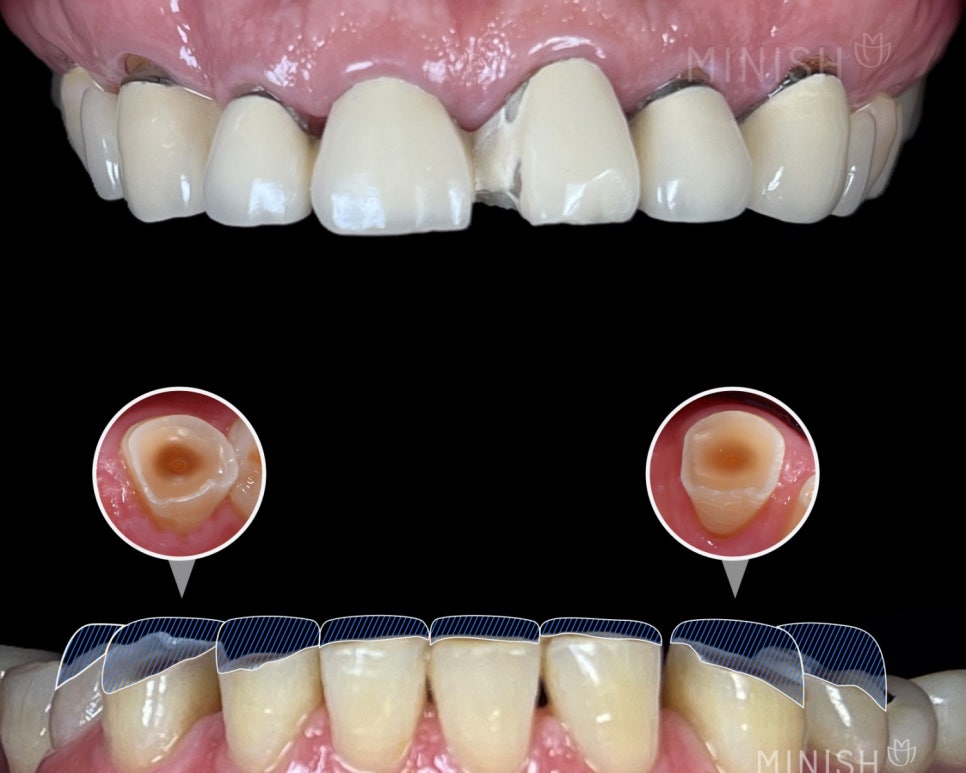

2) “No-Prep Veneers” vs. MINISH: Why Truly No-Shaving Cases Are Rare

“No-prep veneers” suggest zero tooth reduction. In real clinical settings, cases where reduction is truly unnecessary are uncommon. No-prep may be feasible only in limited situations, such as:

- noticeable spacing between teeth (gaps)

- unusually small teeth (microdontia)

In many other cases, some space is needed so the restoration doesn’t look bulky or interfere with bite function—especially if teeth are larger, rotated, or angled. This is similar to orthodontics, where clinicians may create space using techniques like stripping (minor side reduction between teeth).

4) Does MINISH Require Tooth Shaving?

MINISH typically includes surface refinement—a controlled smoothing step to address natural unevenness and micro-cracks on enamel. This helps:

- improve bonding accuracy

- reduce leakage risk

- minimize unnecessary side effects

- strengthen overall adhesion

A simple analogy: makeup adheres better after gentle exfoliation—bonding works similarly when the surface is properly prepared.